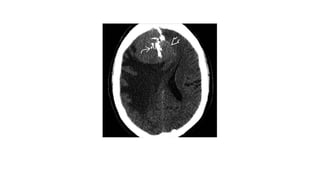

Imaging

• Difficult to predict meningioma tumor grade on imaging

• Imaging findings of typical meningioma do not exclude atypical, malignant

variant

• NECT

CT triad of MM: extracranial mass, osteolysis , intracranial tumour

Marked perifocal edema

• CECT

Enhancing tumour mass

Prominent tumour pannus extending away from mass=mushrooming

MRI

• T1WI

Indistinct tumour margin

Infiltrating tumour interdigitates with brain

• T1WI+C

Enhacing tumour mass

May extend into brain, skull scalp

• FAIR

marked peritumoral edema

• DWI

markedly hyperintense on DWI , hypointense in ADC map